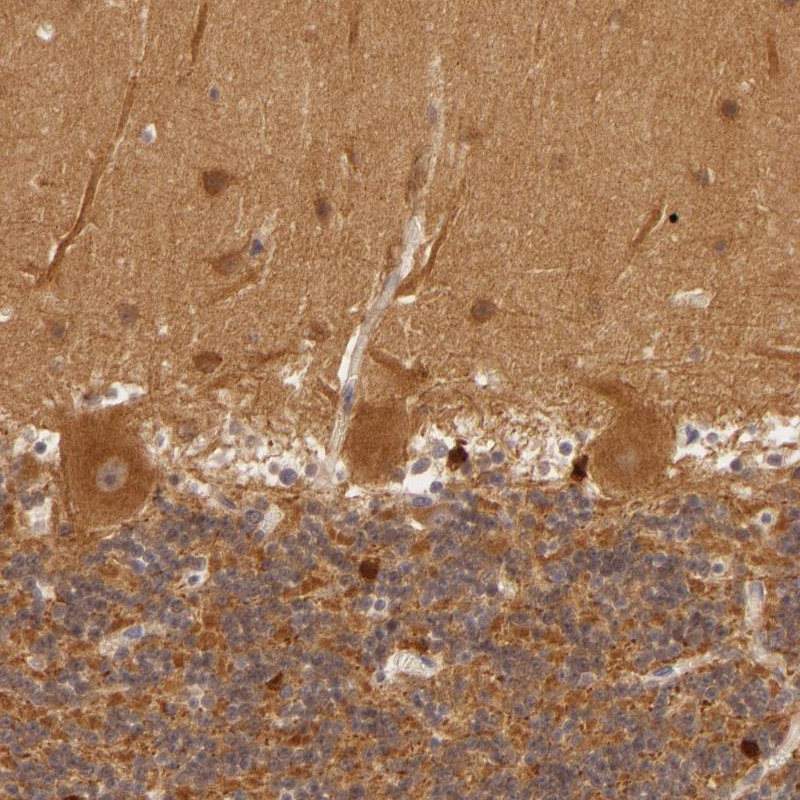

Immunohistochemical staining of human cerebellum shows moderate cytoplasmic positivity in Purkinje cells, cells in molecular layer and cells in granular layer.